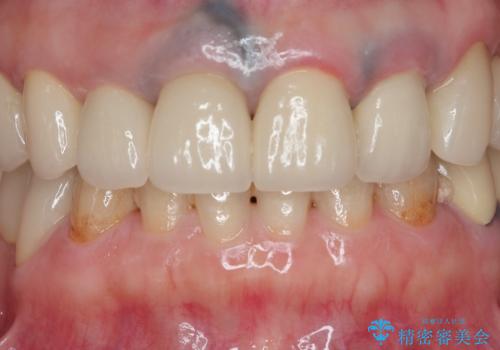

審美的かつ精度の高いセラミック治療を行うことで、汚れがつきにくく虫歯や歯周病の感染リスクを将来にわたって抑える治療が可能になります。

見違えるような審美的な仕上がりに満足いただくことができました。